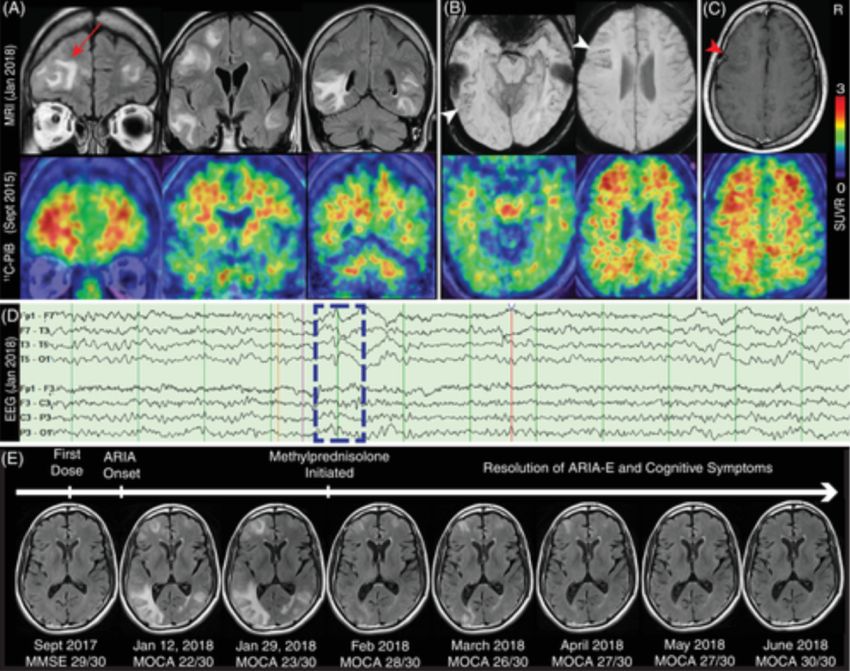

Il lecanemab (Leqembi) è una terapia con anticorpi monoclonali per il morbo di Alzheimer (MA) che elimina le placche amiloidi tossiche e ritarda il declino cognitivo. I ricercatori del VIB e della KU Leuven hanno ora dimostrato per la prima volta il...